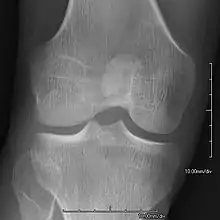

Bones and joints

- Patellar involvement is present in approximately 90% of patients; however, patellar aplasia occurs in only 20%.

- In instances in which the patellae are smaller or luxated, the knees may be unstable.

- Exostoses arising from the posterior aspect of the iliac bones ("iliac horns") are present in as many as 80% of patients; this finding is considered pathognomonic for the syndrome.

An elbow of a man with nail–patella syndrome (NPS)